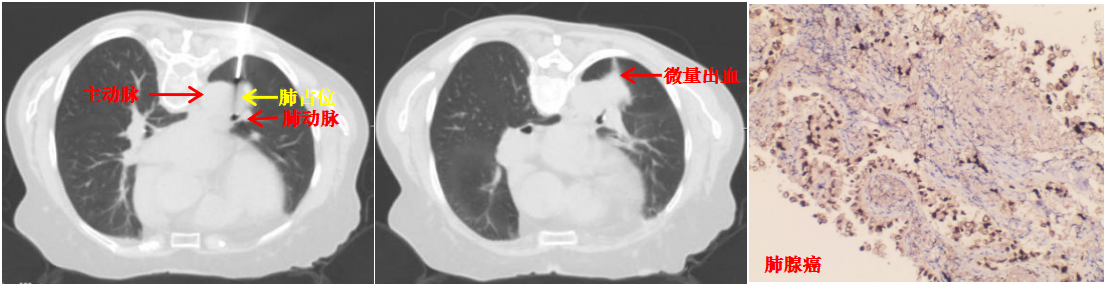

本病例患者肺结节穿刺中(左图)、穿刺后(中图)和病理诊断(右图)

取得患者及家属同意后,陆霓虹主任带领介入团队医生杨嫄、贺晓洁,护士杨红艳、王丽,在CT引导下实施穿刺活检。影像监控下,针尖精准抵达病灶核心,实时测量显示针尖距离主动脉仅4mm,团队迅速完成切割取材,仅出现极少量创面出血,对症处理后患者安返病房,无出血、气胸等并发症。

术后病理确诊为肺腺癌,为患者后续治疗提供了决定性依据。此次技术突破,是科室在高危肺结节诊疗领域的又一跨越。未来,华人色情 呼吸与危重症医学科介入团队将持续精进技术、优化诊疗流程,为更多高危肺结节患者提供精准、安全的微创诊疗服务。